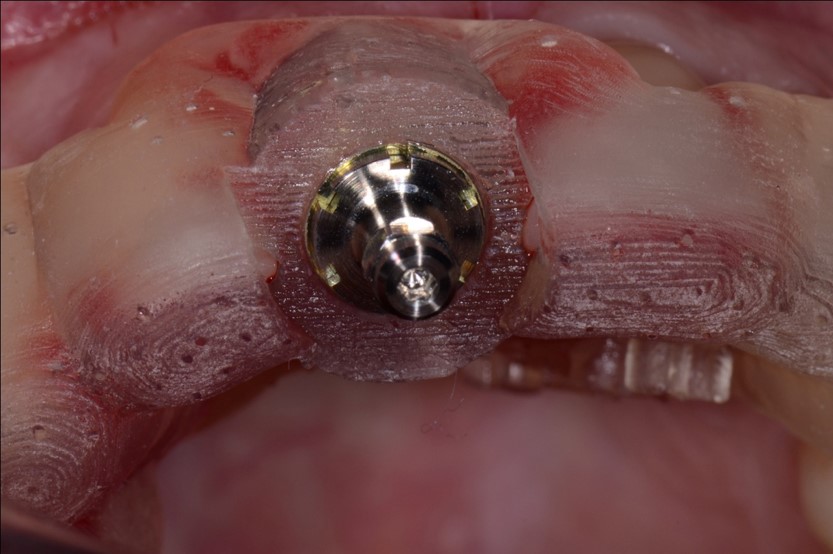

Fig 19. Surgical guide for implant placement.

Figure 19

Fig 20. The implant was placed immediately following extraction according to the treatment plan.

Figure 20

However, by giving consideration to the most appropriate and minimally invasive sequence of care, this led to performing predictable procedures beginning with a tunneling procedure with a small connective tissue graft (Figure 15). Once the connective tissue graft healed (Figure 16), extra soft tissue with a thickened biotype was available. This would enable minimally invasive extraction using piezosurgery—without damaging the soft tissues (Figure 17)—followed by immediate implant placement according to 3D implant treatment planning (Figure 18 through Figure 20).